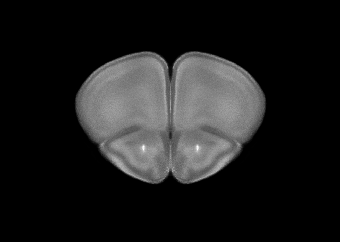

In this study, we sought to allow for template-based segmentation of 2-dimensional mouse brain slices acquired with fluorescence microscopy. Typically, a stain called DAPI is used to show the brain structures, and up to three additional channels are used for measuring the molecule(s) of interest. So, we needed to construct a population-based template of the mouse brain from slices stained with DAPI.

We collected consecutive coronal slices from 12 mice (C57BL/6) covering the majority of the cerebrum and DAPI-stained them. With the help of Allen Mouse Brain Common Coordinate Framework (CCFv3) we were able to reconstruct all 12 brains. This was done by iteratively stacking the 2-dimensional slices into 3-dimensional volumes, registering, and slicing. With the reconstructed brains, we could perform the template creation in 3-dimensional space. Using this new template in combination with the CCFv3 we started over with the reconstruction and template creation resulting in the final well-defined DAPI template (shown in the beginning of the post).

We were thrilled with how well the reconstruction process worked and happy to see a well-defined and smooth template. New coronal slices were easily registered to the template, so we wrote a small python program for automatic template-based segmentation (see the full paper for examples). To encourage the scientific community to utilize and improve the template, we have made all the data available in a well-structured and ordered fashion here: https://doi.org/10.12751/g-node.16wrxa